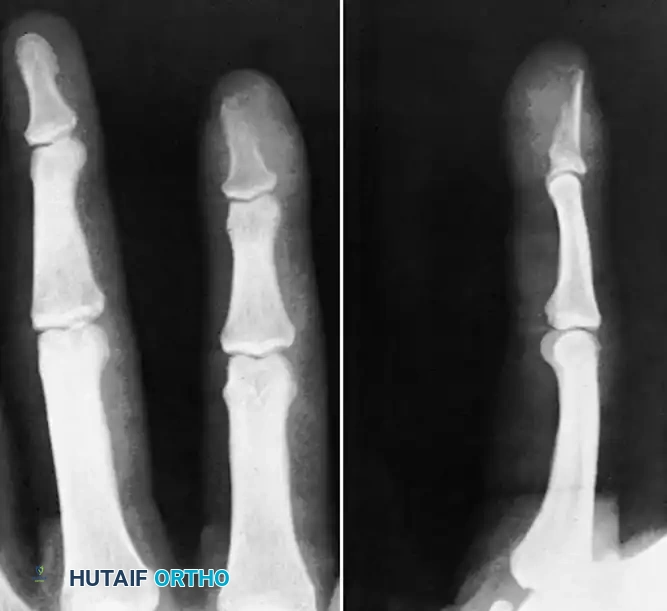

Osteitis and Osteomyelitis

If the infection breaches the subchondral bone, or if a contiguous soft tissue infection (such as a felon in the digital pulp) is left untreated, osteitis and subsequent osteomyelitis will develop.

FIGURE 78-16: Osteitis of the distal phalanx caused by an untreated infection in the finger pulp (felon). Note the lytic destruction and loss of cortical margins at the tuft.

As osteomyelitis progresses, the vascular supply to the bone is compromised by purulent exudate under pressure and septic microthrombi. This leads to ischemic necrosis of the bone, resulting in the formation of a sequestrum (a piece of dead bone that has become separated during the process of necrosis from normal bone).

FIGURE 78-17: Sequestrating osteomyelitis of the middle phalanx. The radiograph demonstrates profound bony destruction, periosteal reaction, and a central radiodense sequestrum surrounded by a radiolucent involucrum.